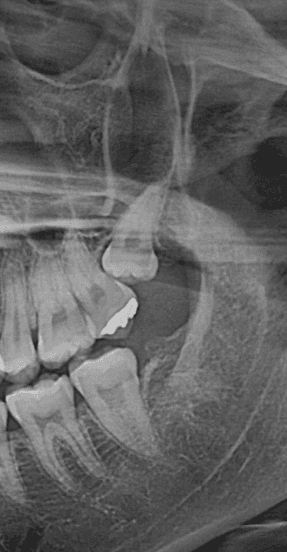

그 이유는 명확합니다. 사랑니는 개인마다 나는 방향, 묻혀 있는 깊이, 뿌리의 형태가 모두 다르며, 이에 따라 발치 난이도가 현저히 달라지기 때문입니다.**

## 사랑니가 난 방향이 난이도를 결정합니다

사랑니가 어느 방향으로 나 있느냐는 발치 난이도에 직접적인 영향을 미치는 핵심 요소입니다.

- 옆으로 누워서 난 경우(수평 매복) → 난이도 증가

- 잇몸깊은 곳을 향해 난 경우 → 고난도 수술

특히 잇몸 방향으로 향한 사랑니는, 치아가 자연적으로 이동하려는 방향 자체가 뼈 안쪽이기 때문에 발치 시 매우 까다로운 술식이 요구됩니다.

첨부 이미지

사랑니 발치, 얼마나 걸릴까? 시간과 비용의 모든 것 - 이미지 1